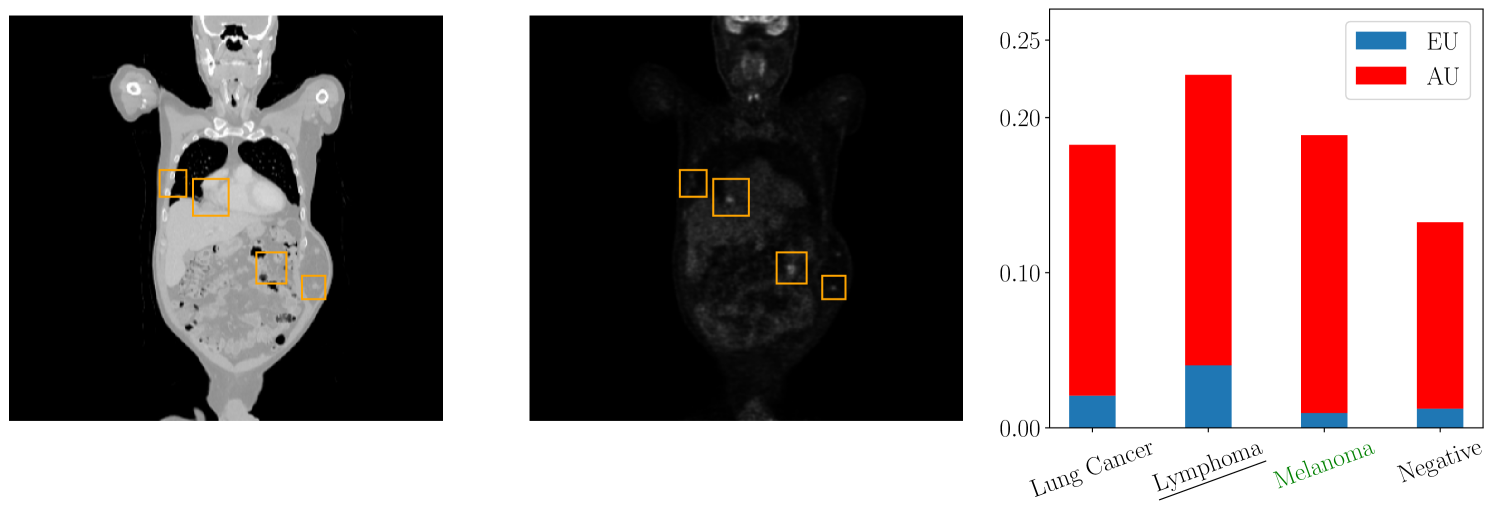

For the evaluation in the medical domain, we use a data set of Positron Emission Tomography/Computed Tomography (PET/CT) images which comprises 501 full-body scans from patients with malignant lymphoma, melanoma, and lung cancer, as well as 513 scans from individuals without malignant lesions (negative controls) [Gatidis et al., 2022]. Each scan is annotated with a tumor segmentation performed by a medical expert. We extract from each 3D CT and PET volume multiple 2D images which are used to train a deep neural network ensemble and evaluate the label-wise uncertainty quantification.

Figure 2 depicts a qualitative example of a 2D PET/CT image from the data set with the corresponding label-wise uncertainties from our evaluation. We observe low aleatoric uncertainty and negligible epistemic uncertainty for the melanoma class. This implies that the approximation of the aleatoric uncertainty is reliable. On the contrary, the classes lung cancer and lymphoma are associated with high aleatoric and high epistemic uncertainty, suggesting that the prediction with respect to these classes may not be accurate. This observation is plausible from a medical perspective as we observe multiple tumors in the image which are not limited to the lung area and thus might indicate a different tumor class as well. In this instance, we could request a medical expert to annotate additional data for the classes lung cancer and lymphoma, thereby diminishing the epistemic uncertainty associated with these classes. Here, a global measure of uncertainty would only give epistemic uncertainty with respect to all classes, meaning a doctor would have to annotate data for all classes.

Having a more detailed understanding of the label-wise uncertainties is crucial for the decision-making in medical applications supporting a given diagnosis. Moreover, it allocates resources to the relevant classes and saves valuable examination time and costs.

Figure 4 presents additional medical images with the highest total, aleatoric, and epistemic uncertainties. Similarly, Figure 5 showcases images with the highest total, aleatoric, and epistemic uncertainties for the MNIST data set.